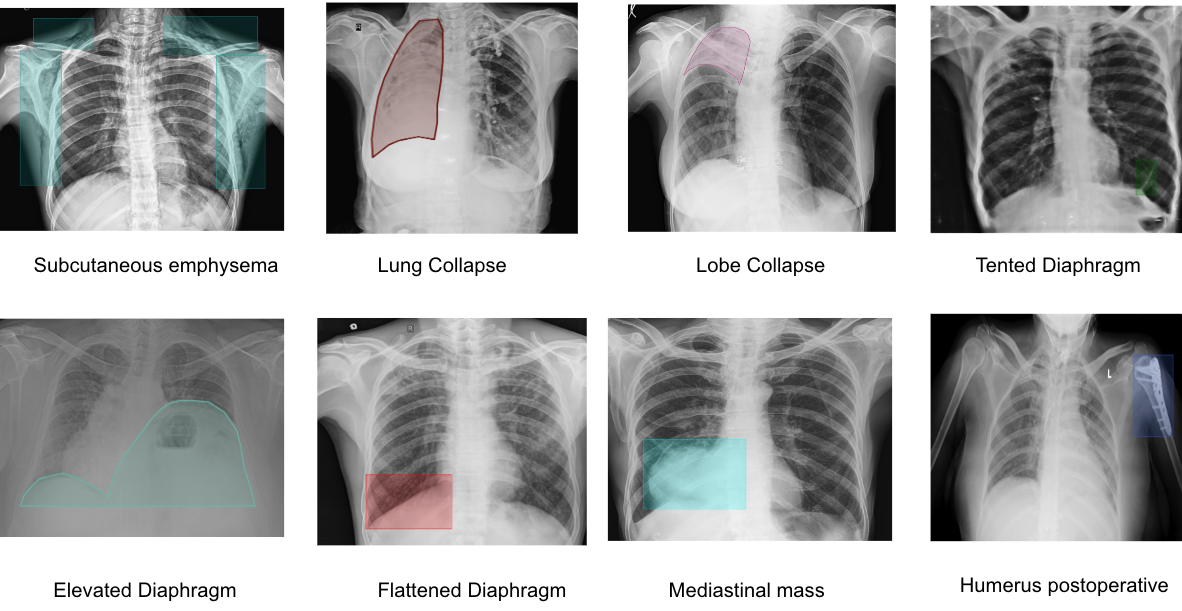

This paper presents an AI-based approach designed to address these challenges in the Indian healthcare system by enhancing CXR pathology detection capabilities. The system is capable of detecting 75 distinct pathologies, from common infections to complex thoracic conditions, using a combination of Vision Transformers for classification, Faster R-CNN for detection, and UNet for segmentation [5]. This multi-layered approach enables precise identification of abnormalities while automating the detection and reporting process. We begin by outlining the challenges in CXR reporting within India and describe how AI is uniquely positioned to tackle these issues [6]. The paper also elaborates on the methodology, covering the system architecture and workflow from input to pathology detection, aimed at providing accurate and actionable insights [7].

The AI system developed for this study is a computer-aided detection (CAD) tool designed for the identification and differentiation of various radiological abnormalities present in chest X-rays (CXRs). This system incorporates multiple deep-learning algorithms, each tailored to detect specific pathologies, covering a comprehensive range of thoracic conditions(Ronneberger et al., 2015). The models were trained on a large-scale dataset consisting of over 5 million CXR images, with expert radiologist annotations used for supervised learning(Firdiantika & Jusman, 2022). The AI system aims to detect abnormalities such as lung nodules, pleural effusion, pneumothorax, cardiomegaly, consolidation, fibrosis, hilar enlargement, rib fractures, etc.

Moving beyond classification, the detection capability of the model was evaluated using Precision, Recall, and Intersection over Union(IoU) metrics. Precision indicates how many of the abnormalities identified by the model were true positives, while recall measures the ability of the model to identify all existing abnormalities in the chest X-rays. IoU was utilized to evaluate the overlap between predicted regions of interest and the actual ground truth, offering a quantitative assessment of the model’s localization accuracy. Performance metrics for all 75 detected pathologies were documented, providing an in-depth view of how well the system performed for each specific condition. The metrics for precision, recall for each of these pathologies are presented in the table below, showcasing the AI’s proficiency in both identifying and accurately localizing abnormalities. These results highlight the system’s ability to support clinical workflows, enhancing both the accuracy and speed of radiology reporting.